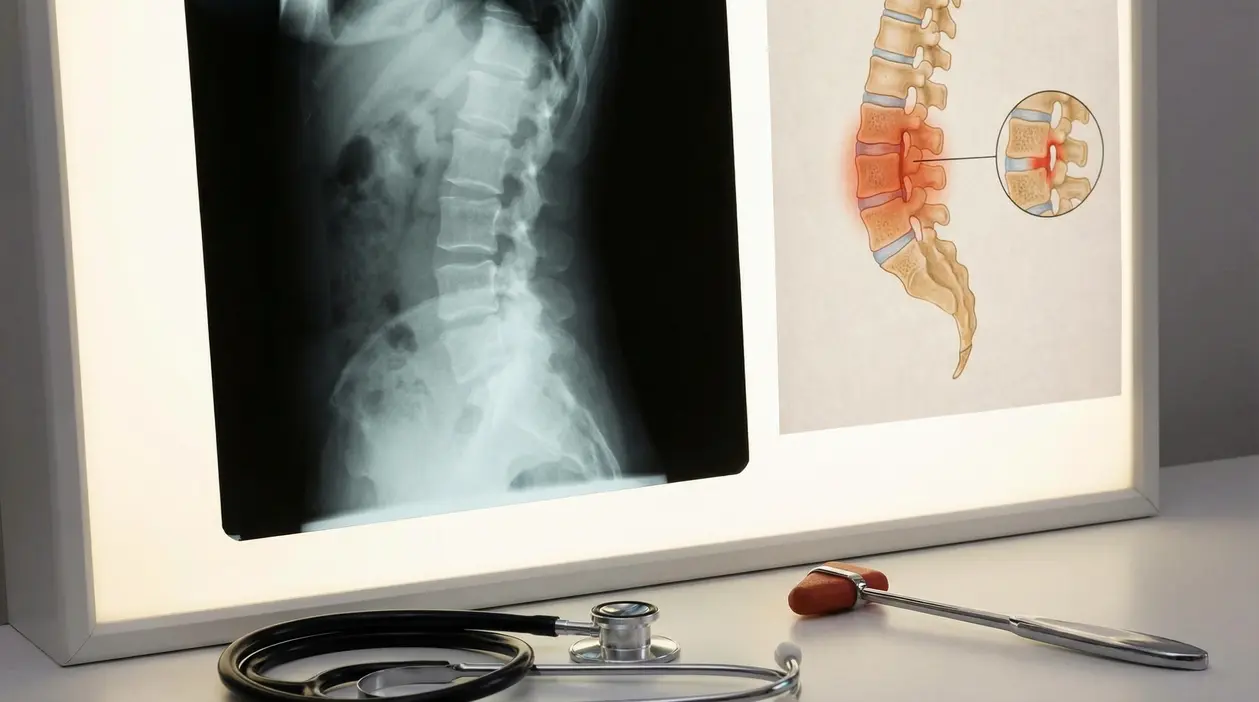

- la risonanza, molto utile per vedere l’infiammazione in fase precoce

- le radiografie, che mostrano meglio i danni più avanzati